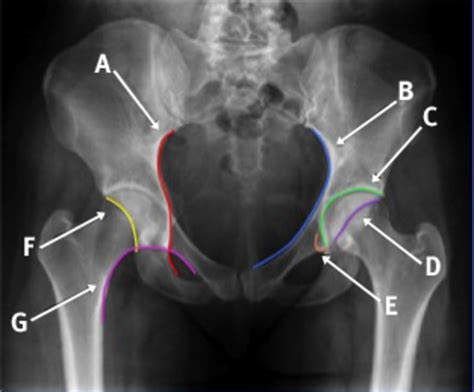

Interpreting Normal Hip X Rays requires a trained eye and a thorough understanding of hip anatomy. Radiologists look for specific features and measurements to determine the health of the hip joint. Key areas of focus include:

Radiologists use specific measurements and comparisons to assess the hip joint. For example, the Sharp angle and the center-edge angle are commonly used to evaluate the acetabular coverage of the femoral head. These angles help determine if the hip joint is properly aligned and functioning correctly.